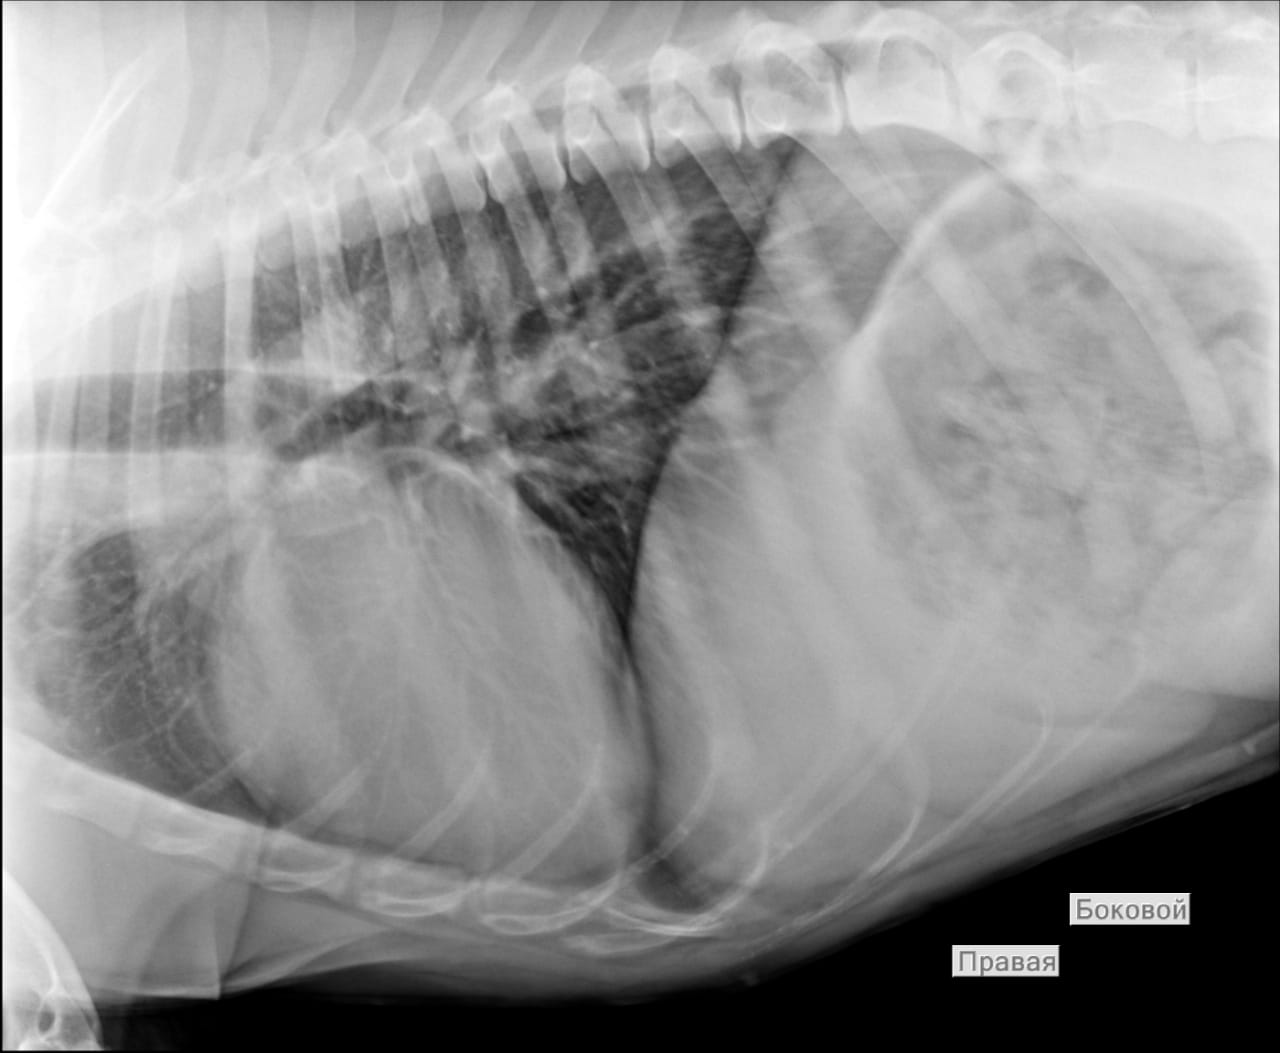

Анализы Арчи. Сердца и легких

Сегодня Арчуна Ирина возила на рентген легких и сдали анализ мочи. Результат анализа мочи готов будет завтра. Рентген легких выставляю.

Ирина, ждем твоего вердикта по рентгена и можно ли нам готовить Арчи к операции по глазам.

Антибиотика курс пропили.

Лучше чем было, но явно не норма:(